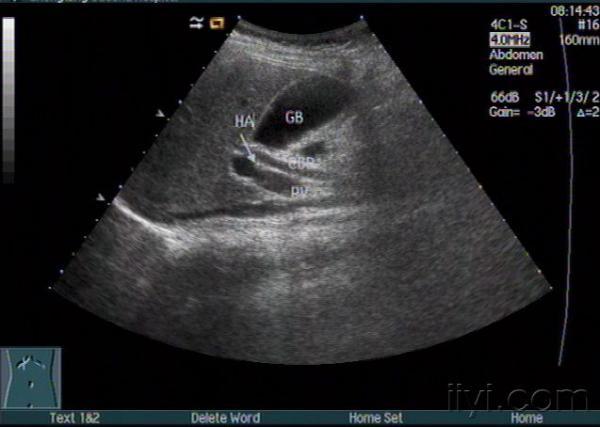

胆道闭锁?

小儿黄疸,是胆道闭锁吗??

太难了,本身就很细了,追踪下去难度很大的,而且探头稍微歪曲就有可能看错。不知此病例进一步检查确诊了没有?

图像没有胆道闭锁的征象啊!越来越不易啊